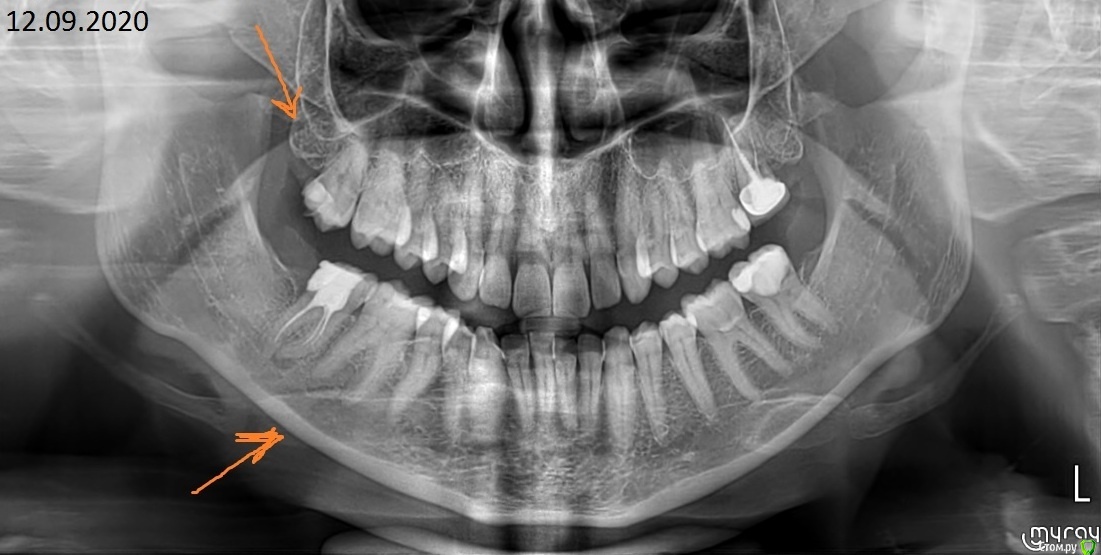

Ортопантомограмма сентября - до чистки каналов 17 зуба

Понять, в 27, 47 - обломки инструмента, уплотненный материал или что видно на КТ...

27 зуб, лучше видно все на КТ

Есть ли обломок инструмента в канале?

47

Обломок 3мм на сгибе в канале или нет?